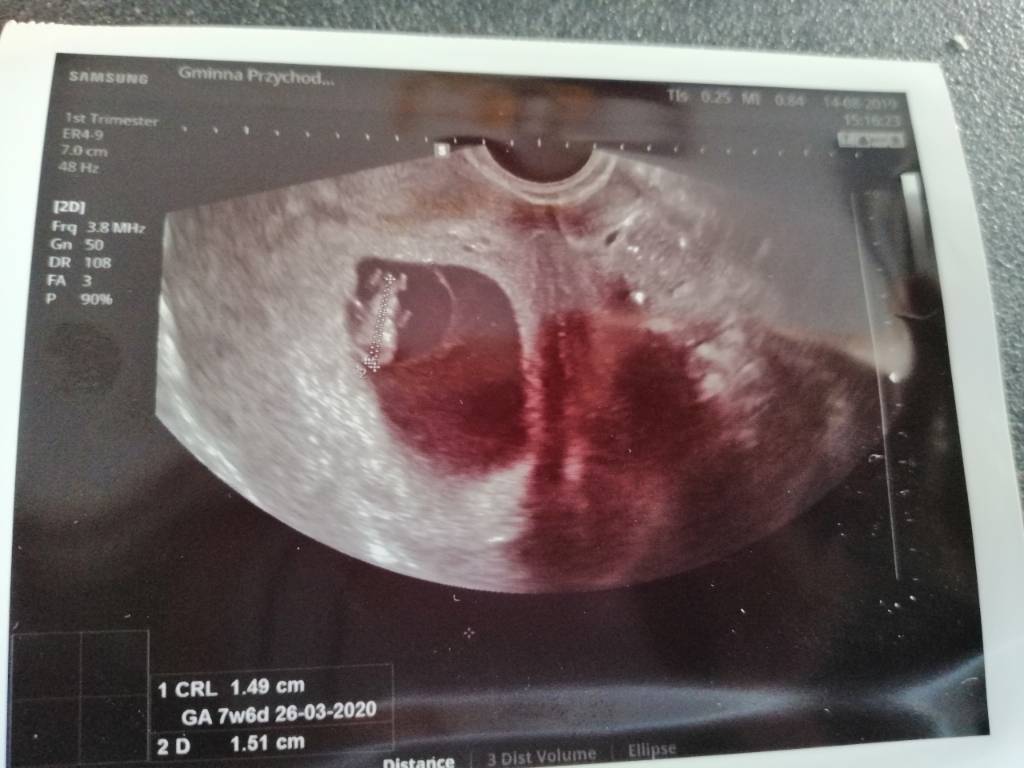

czy to zdjecie to lustrzane odbicie czy faktyczny obraz? Na moim usg wychodzi, ze dzidzia jest z lewej strony, ale przyjelam, ze to lustrzane odbicie czyli w rzeczywistosci jest z prawej.

Zobacz załącznik 1012065